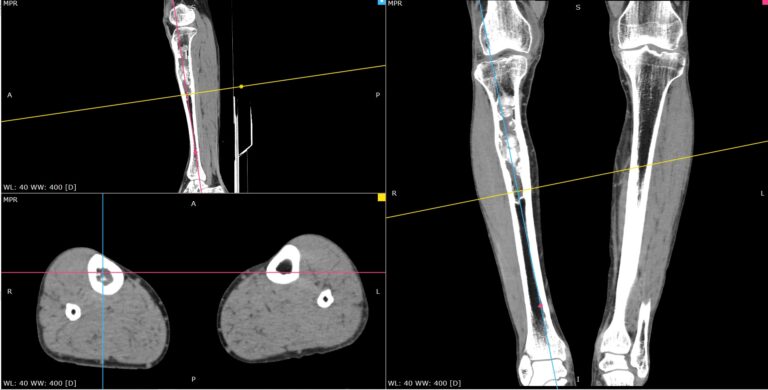

Мультиспиральная компьютерная томография является современным лучевым методом исследования, который позволяет с помощью рентгеновского излучения получить посрезовые снимки и после цифровой обработки создать объемные модели исследуемой области в мельчайших подробностях. Рентгеновские лучи в большей степени поглощаются плотными тканями организма, поэтому на снимках хорошо визуализируются кости скелета. Для более детальной оценки состояния мягкотканных структур зачастую проводится контрастное усиление.

В наших медицинских центрах КТ мягких тканей конечностей выполняется на современных мультиспиральных компьютерных томографах экспертного уровня TOSHIBA AQUILION. Аппараты послойно сканируют область исследования, одномоментно выполняя множество тончайших срезов. В результате получаются снимки высокого качества и трехмерные модели с изображением костного скелета и мягких тканей конечностей. При этом методика скоростного мультисрезового сканирования обеспечивает минимальную дозу рентгеновского облучения для пациента.